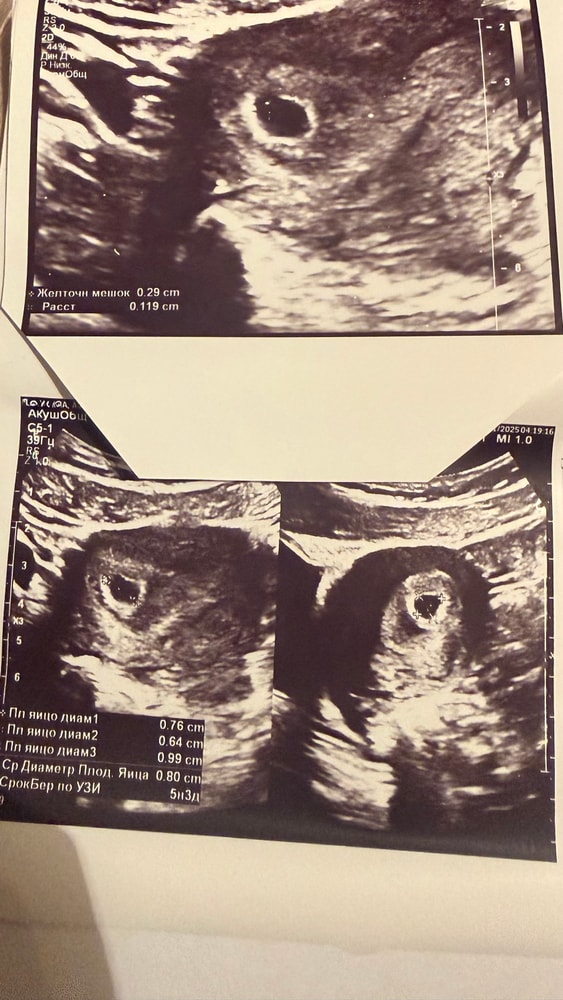

Мне сегодня гинеколог сказала что более 5 мм и не должен расти